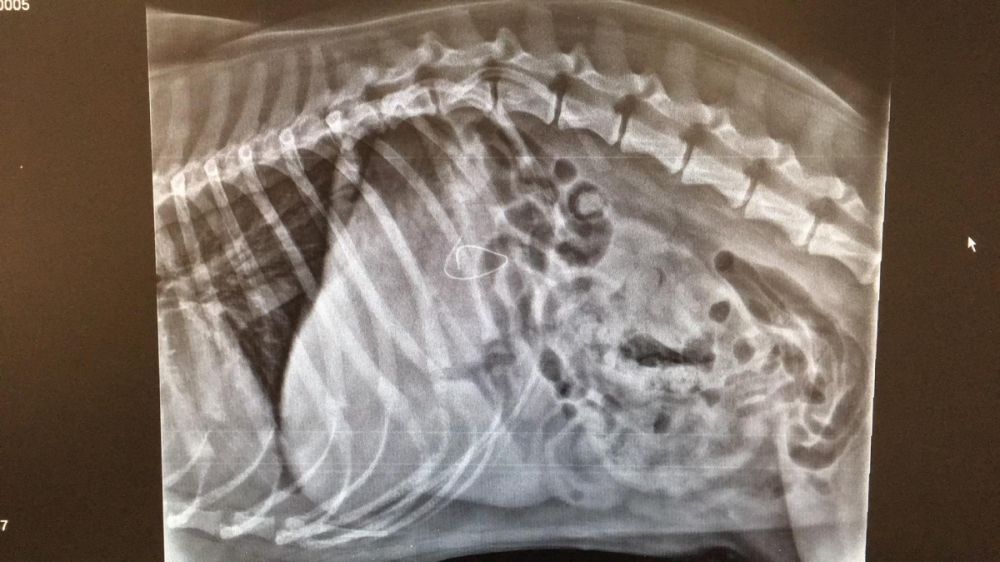

Nous avons constaté, via une radio, un corps étranger dans son système digestif. Nous voyons clairement à la radio la barre métallique présente dans le masque chirurgical.